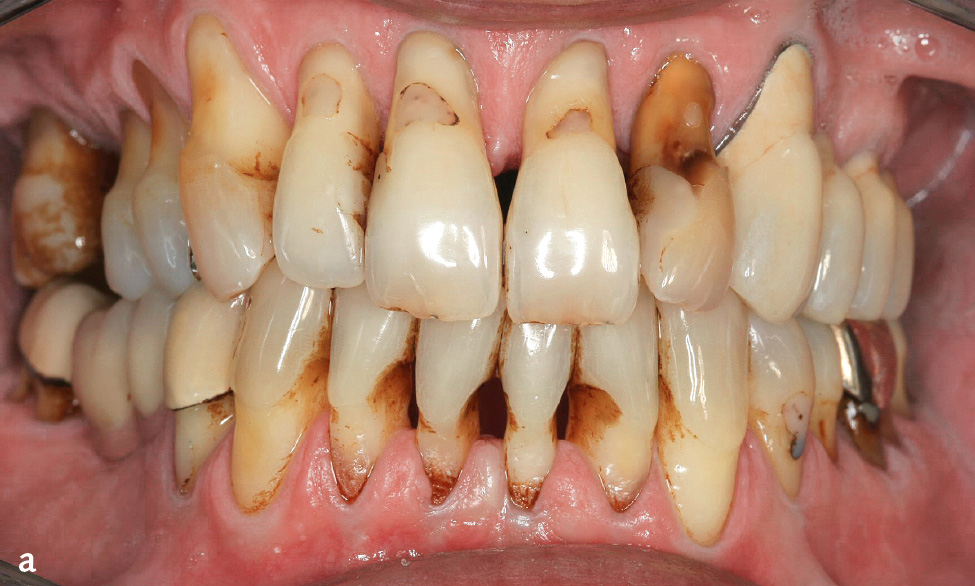

Abb. 6a und b Mann im Alter von 60 bzw. 61 Jahren, starker Raucher, Parodontitis, generalisiertes Stadium IV, Grad C; 1962 bis 1995 20 Zigaretten/Tag, seit 1995 10 Zigaretten/Tag (etwa 44 Packungsjahre): a) Klinische Ansicht im Alter von 61 Jahren; b) Panoramaschichtaufnahme im Alter von 60 Jahren.